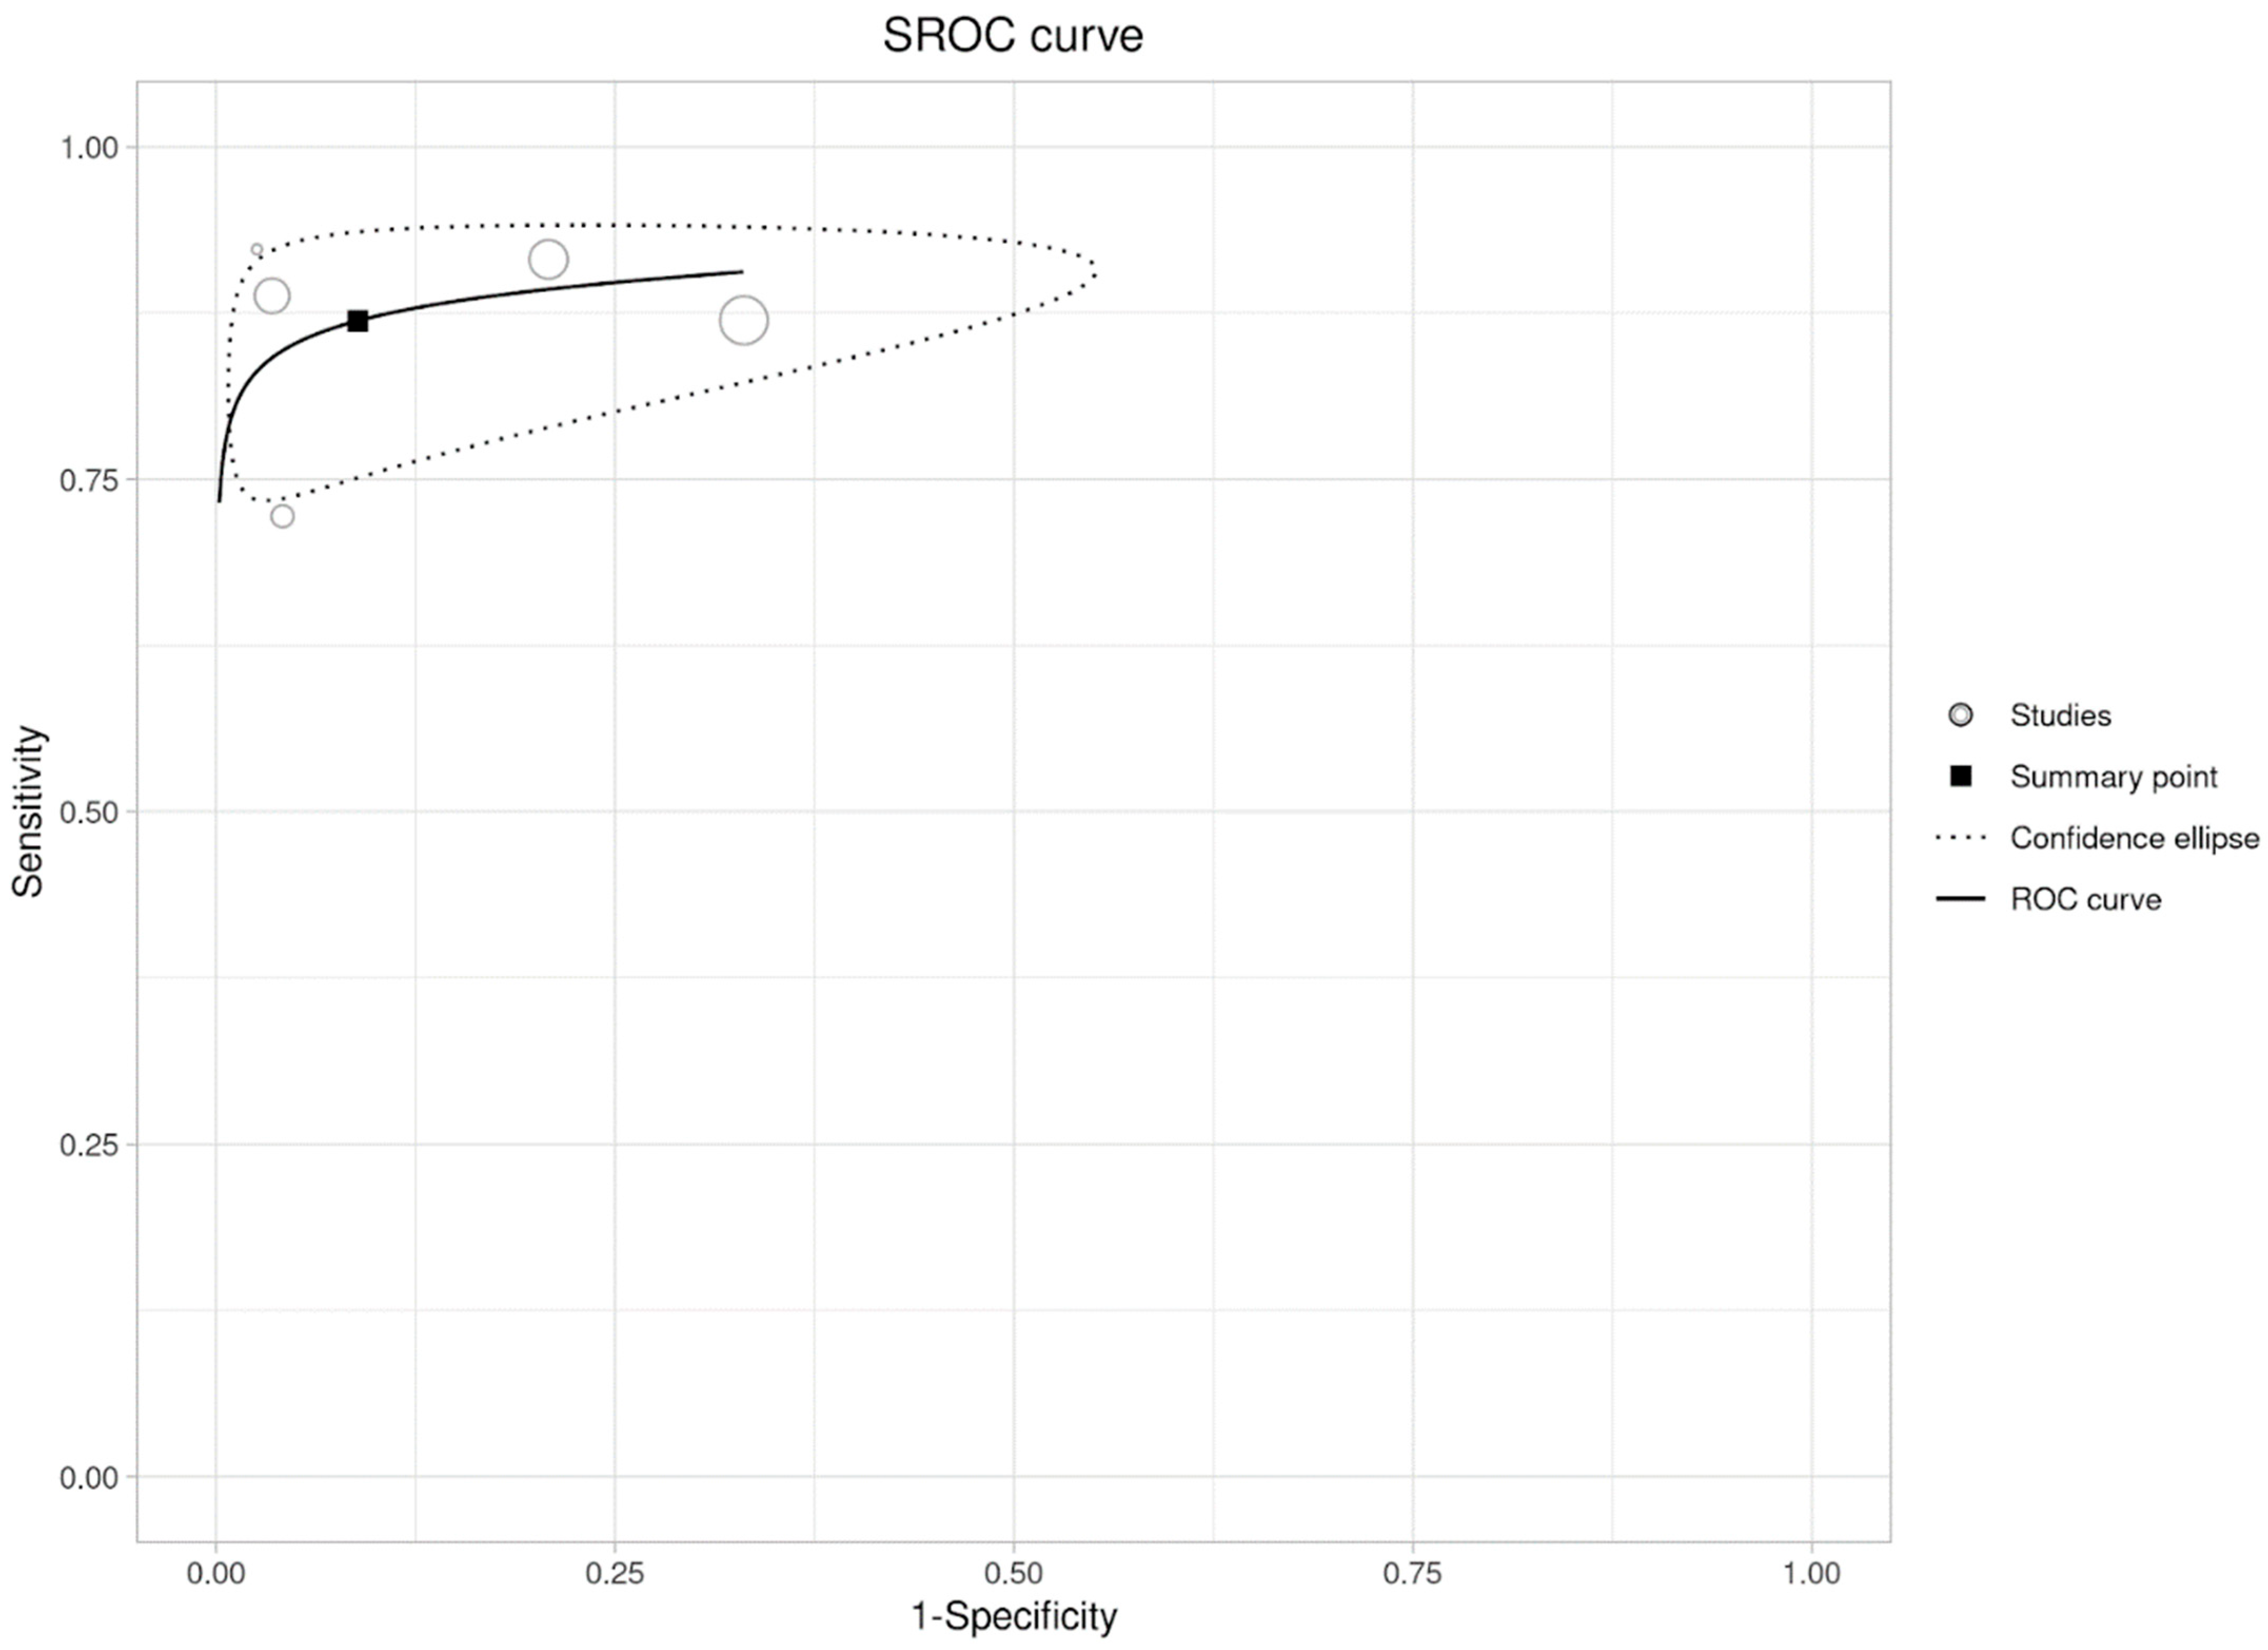

2.4. Statistical Analysis

3.3. Per-Lesion Analysis